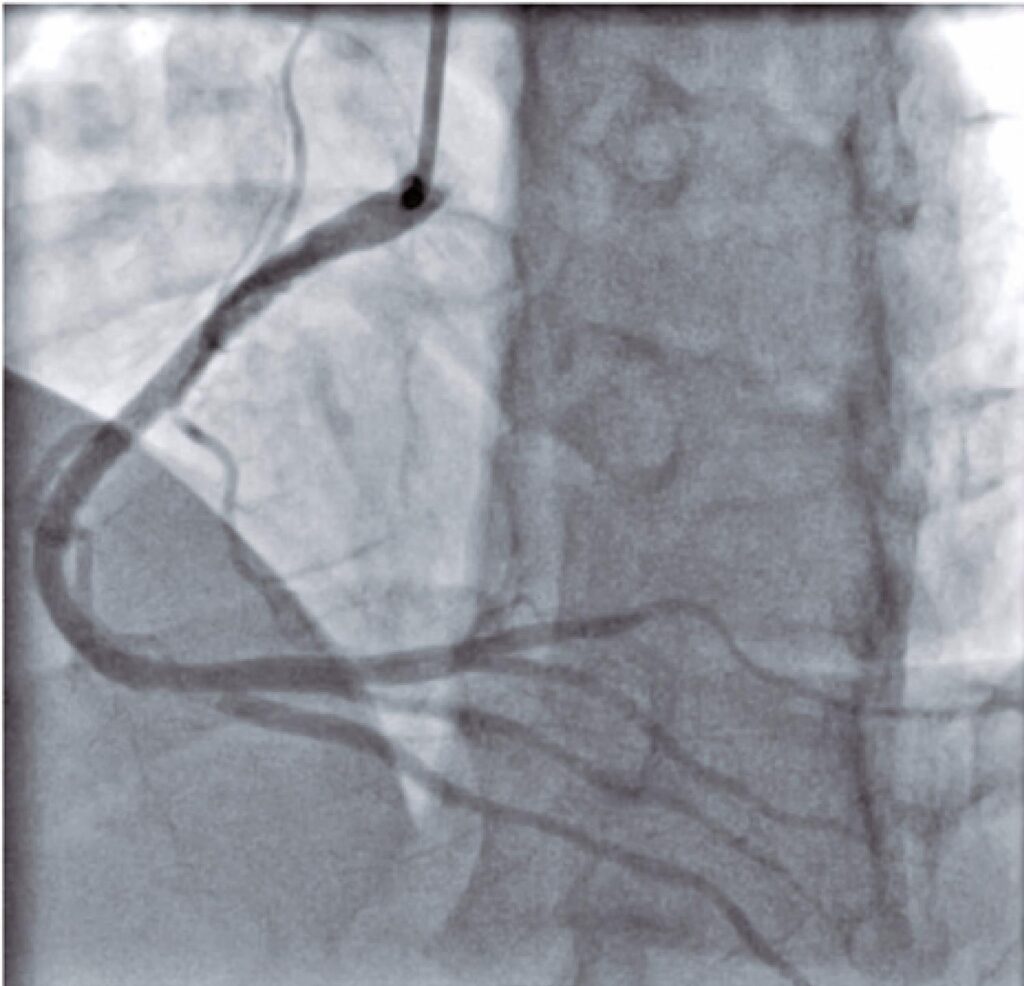

Coronary thrombosis after COVID-19 infection in a young patient with no comorbidities

COVID-19 emerged as a viral infection causing severe acute respiratory syndrome, taking global proportions in 2020, with significant impact on public health. The scenario has become alarming since the infection is more severe in patients with cardiovascular diseases, mortality being up to four-fold greater in these patients, as compared to the general population. As a probable contributor, the prothrombotic inflammatory state has been subject of discussion among scientists, with no consolidated treatments in the short and long term. We describe the case of a young patient, with no cardiovascular risk factors, with ST-segment elevation myocardial infarction caused by coronary thrombosis, in the late period after COVID-19 infection, and reviewed the most recent recommendations for its treatment.